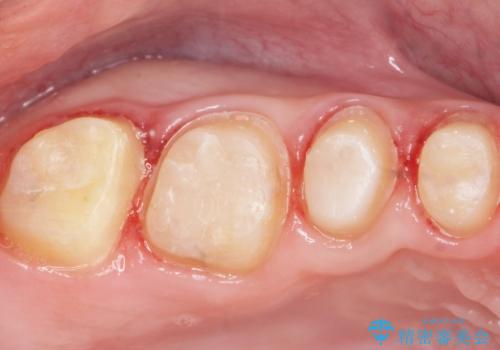

見た目と咬み合わせを改善するため、セラミッククラウンによる治療を行いました。

クラウンの種類:オールセラミッククラウン スタンダード